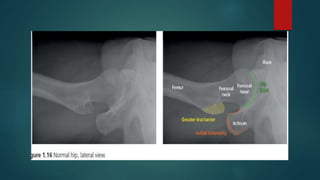

Skeletal X ray anatomy ,colour description, Imaging anatomy of musculoskeletal X rays, Diagnosis imaging anatomay, Radiology